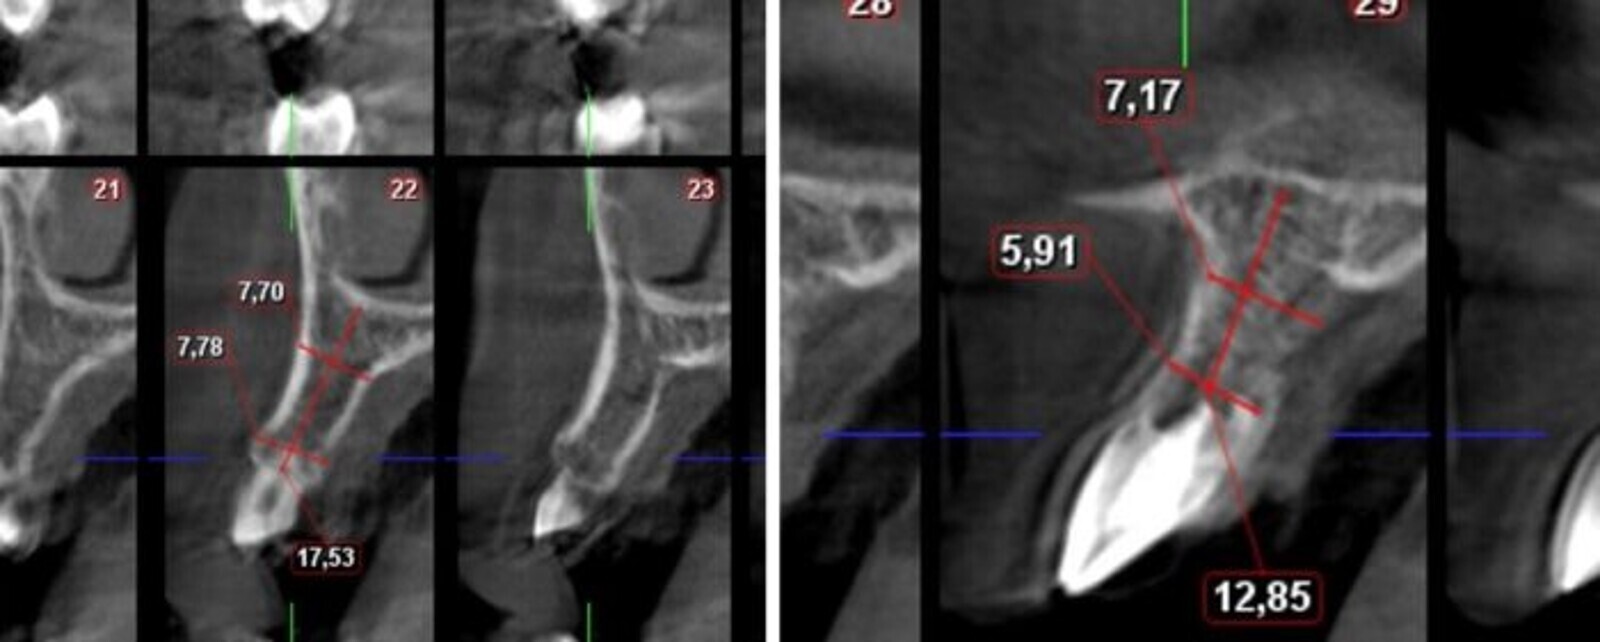

Fig. 3. Tomografía Cone Beam con las mediciones apropiadas.